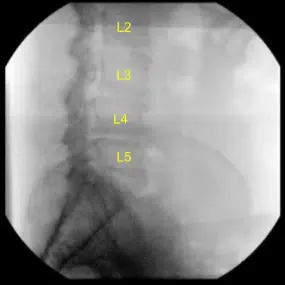

Radiografía intraoperatoria

Se utilizaron radiografías AP y laterales para posicionarlo en una posición verdaderamente lateral y en posición AP, con sus procesos espinosos equidistantes de los pedículos y con sus placas residuales nítidas en fluoroscopia lateral. La posición del flanco izquierdo se fregó cuidadosamente, preparó y colocó tras marcar dos incisiones transversales separadas sobre los espacios discales L3-L4 y L4-L5 bajo fluoroscopia.